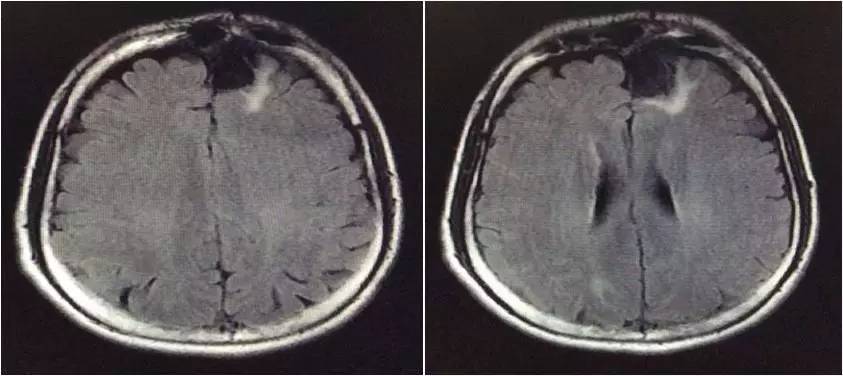

▼头颅MRI

2.脑脊液改变不除外结核感染,但头MRI改变非典型结核影像。左额叶病灶似以脑外为主,波及对侧及额窦,不排除慢性感染病灶急性破入蛛网膜下腔。左额叶病灶与脑脊液信号等信号,DWI也为低信号,说明非急性病变。

嗯,我们用的是国产的头孢曲松,没有进口的罗氏芬。DWI的高信号可以用血管炎解释吗?

血管炎都是多灶的,那个高信号太局限了,就是核心病灶周围的组织反应。不像血管炎。

真菌或结核可以引起脑底血管深穿支的炎症,有类似腔梗的影像改变。